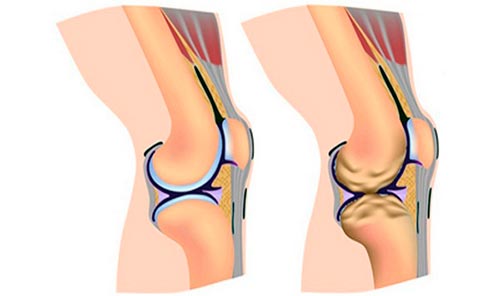

Остеоартроз(гонартроз) –заболевание коленного сустава, по мере развития которого хрящи разрушаются, а сустав теряет функциональность. На первых этапах гонартроза правого или левого колена нарушения происходят на уровне молекул. После приходит очередь гиалинового хряща. Он становится тонким и покрывается трещинками. Далее хрящ полностью исчезает, оставляя кость обнаженной.

При 1 степени боль ощущается только при движении. В покое она сразу проходит. В суставной полости скапливается небольшое количество жидкости. Хрящи уже претерпевают изменения, однако внешне это никак не проявляется.

Гонартроз(остеоартрит коленного сустава) 2 степени: рентгеновский снимок покажет разрастание костной ткани. Во время любых движений чувствуется сильная боль. Она не прекращается даже в состоянии покоя. Отчетливо слышен хруст. Колени теряют свою функциональность. При внешнем осмотре врач видит деформацию.

Остеоартроз колена3 степени:хрящи настолько истончены, что обнажают кость. В пораженных участках откладываются соли, что приводит к появлению остеофитов. Деформированное соединение постоянно болит. При диагнозе артроз колена симптомы и лечение усложняется и боли выражены максимально сильно.